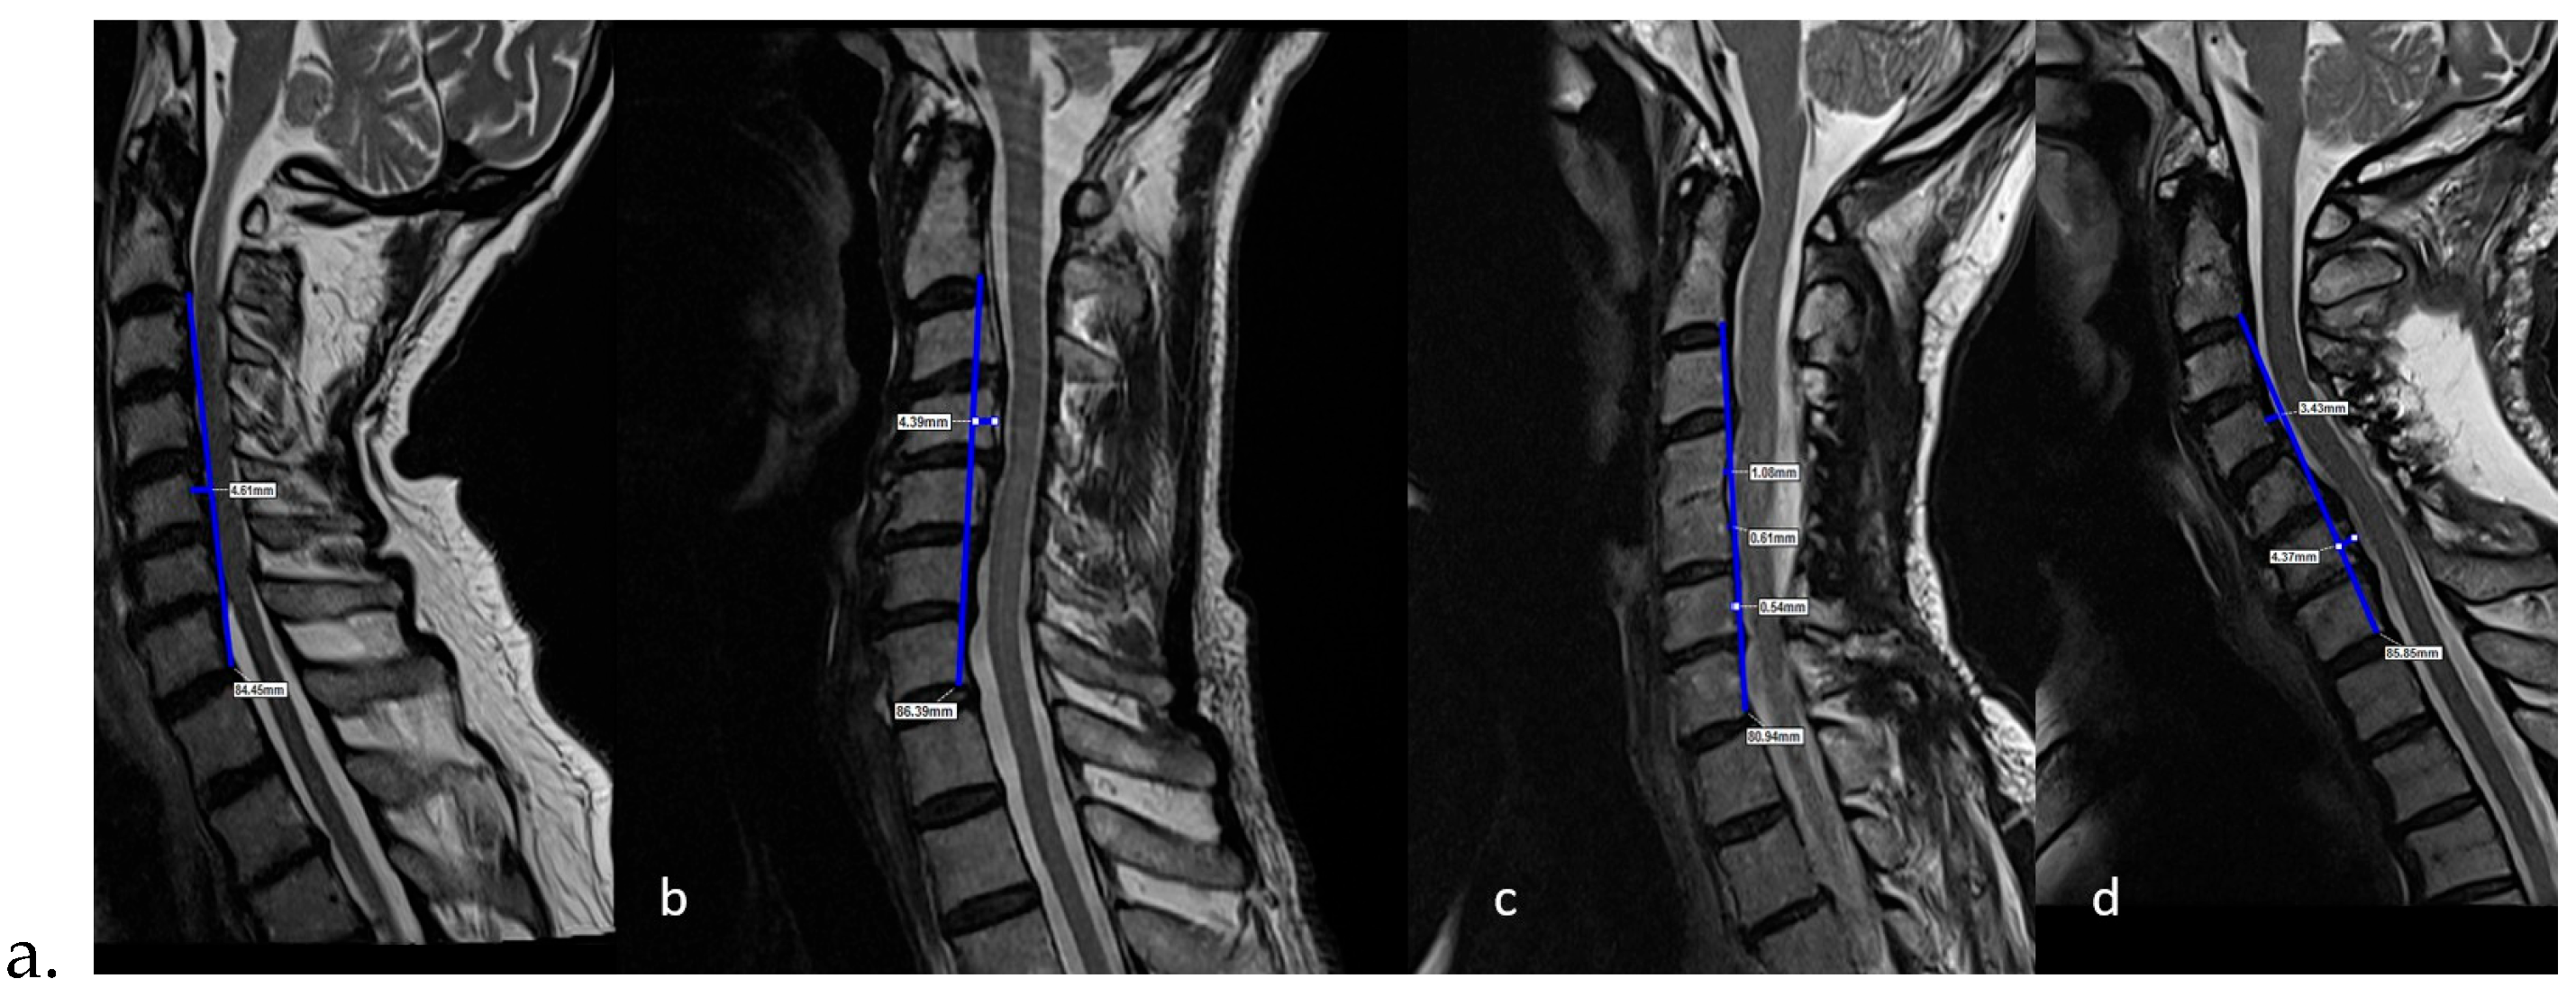

Preoperative K-Line vs. Postoperative K-Line

4.2. Role of Preoperative Lordosis